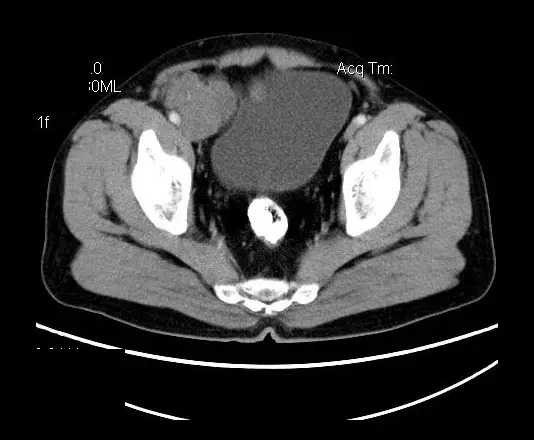

【影像表现】

盆腔右前侧及邻近腹股沟区可见多发大小不等的聚集生长的结节影,病灶呈软组织密度,边缘尚规整,分界尚清,增强扫描可见不均匀强化。膀胱局部受压,盆腔未见明显肿大淋巴结影。